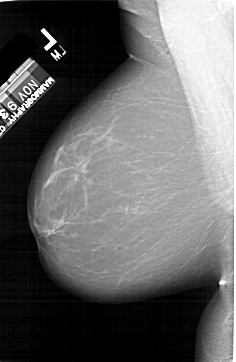

A_1412_1.LEFT_MLO

LEFT_MLO LINES 6511 PIXELS_PER_LINE 4246 BITS_PER_PIXEL 12 RESOLUTION 43.5 NON_OVERLAY